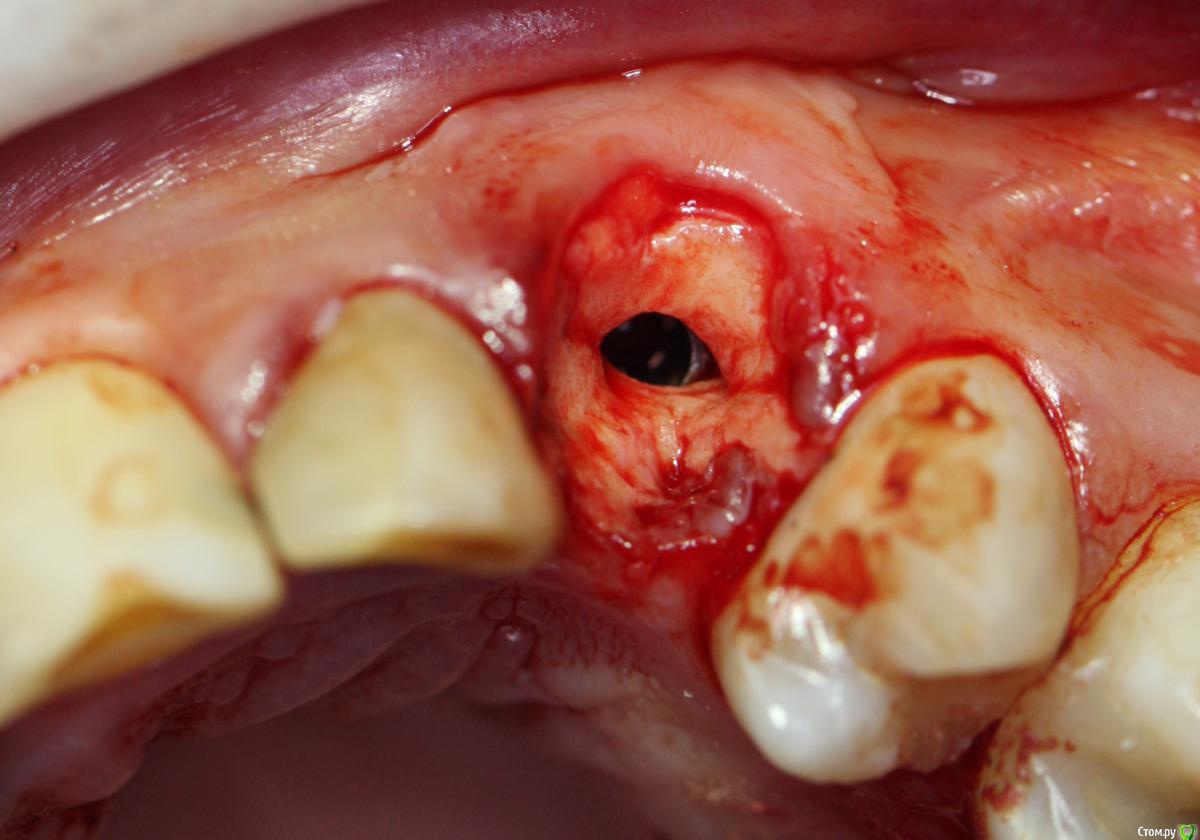

АнтонТЛТ Опубликовано 22 февраля, 2016 Поделиться Опубликовано 22 февраля, 2016 О чём думал врач? http://i74.fastpic.ru/big/2016/0222/1a/f8b52064b580d3fcfab13109a05df91a.jpg 2 Ссылка на комментарий

Doc Опубликовано 24 февраля, 2016 Поделиться Опубликовано 24 февраля, 2016 О чём думал врач?О птичках поёт птицелов,О рыбках поёт рыболов,А я о пиявках пою,За денежки их продаю. (с) 2 Ссылка на комментарий